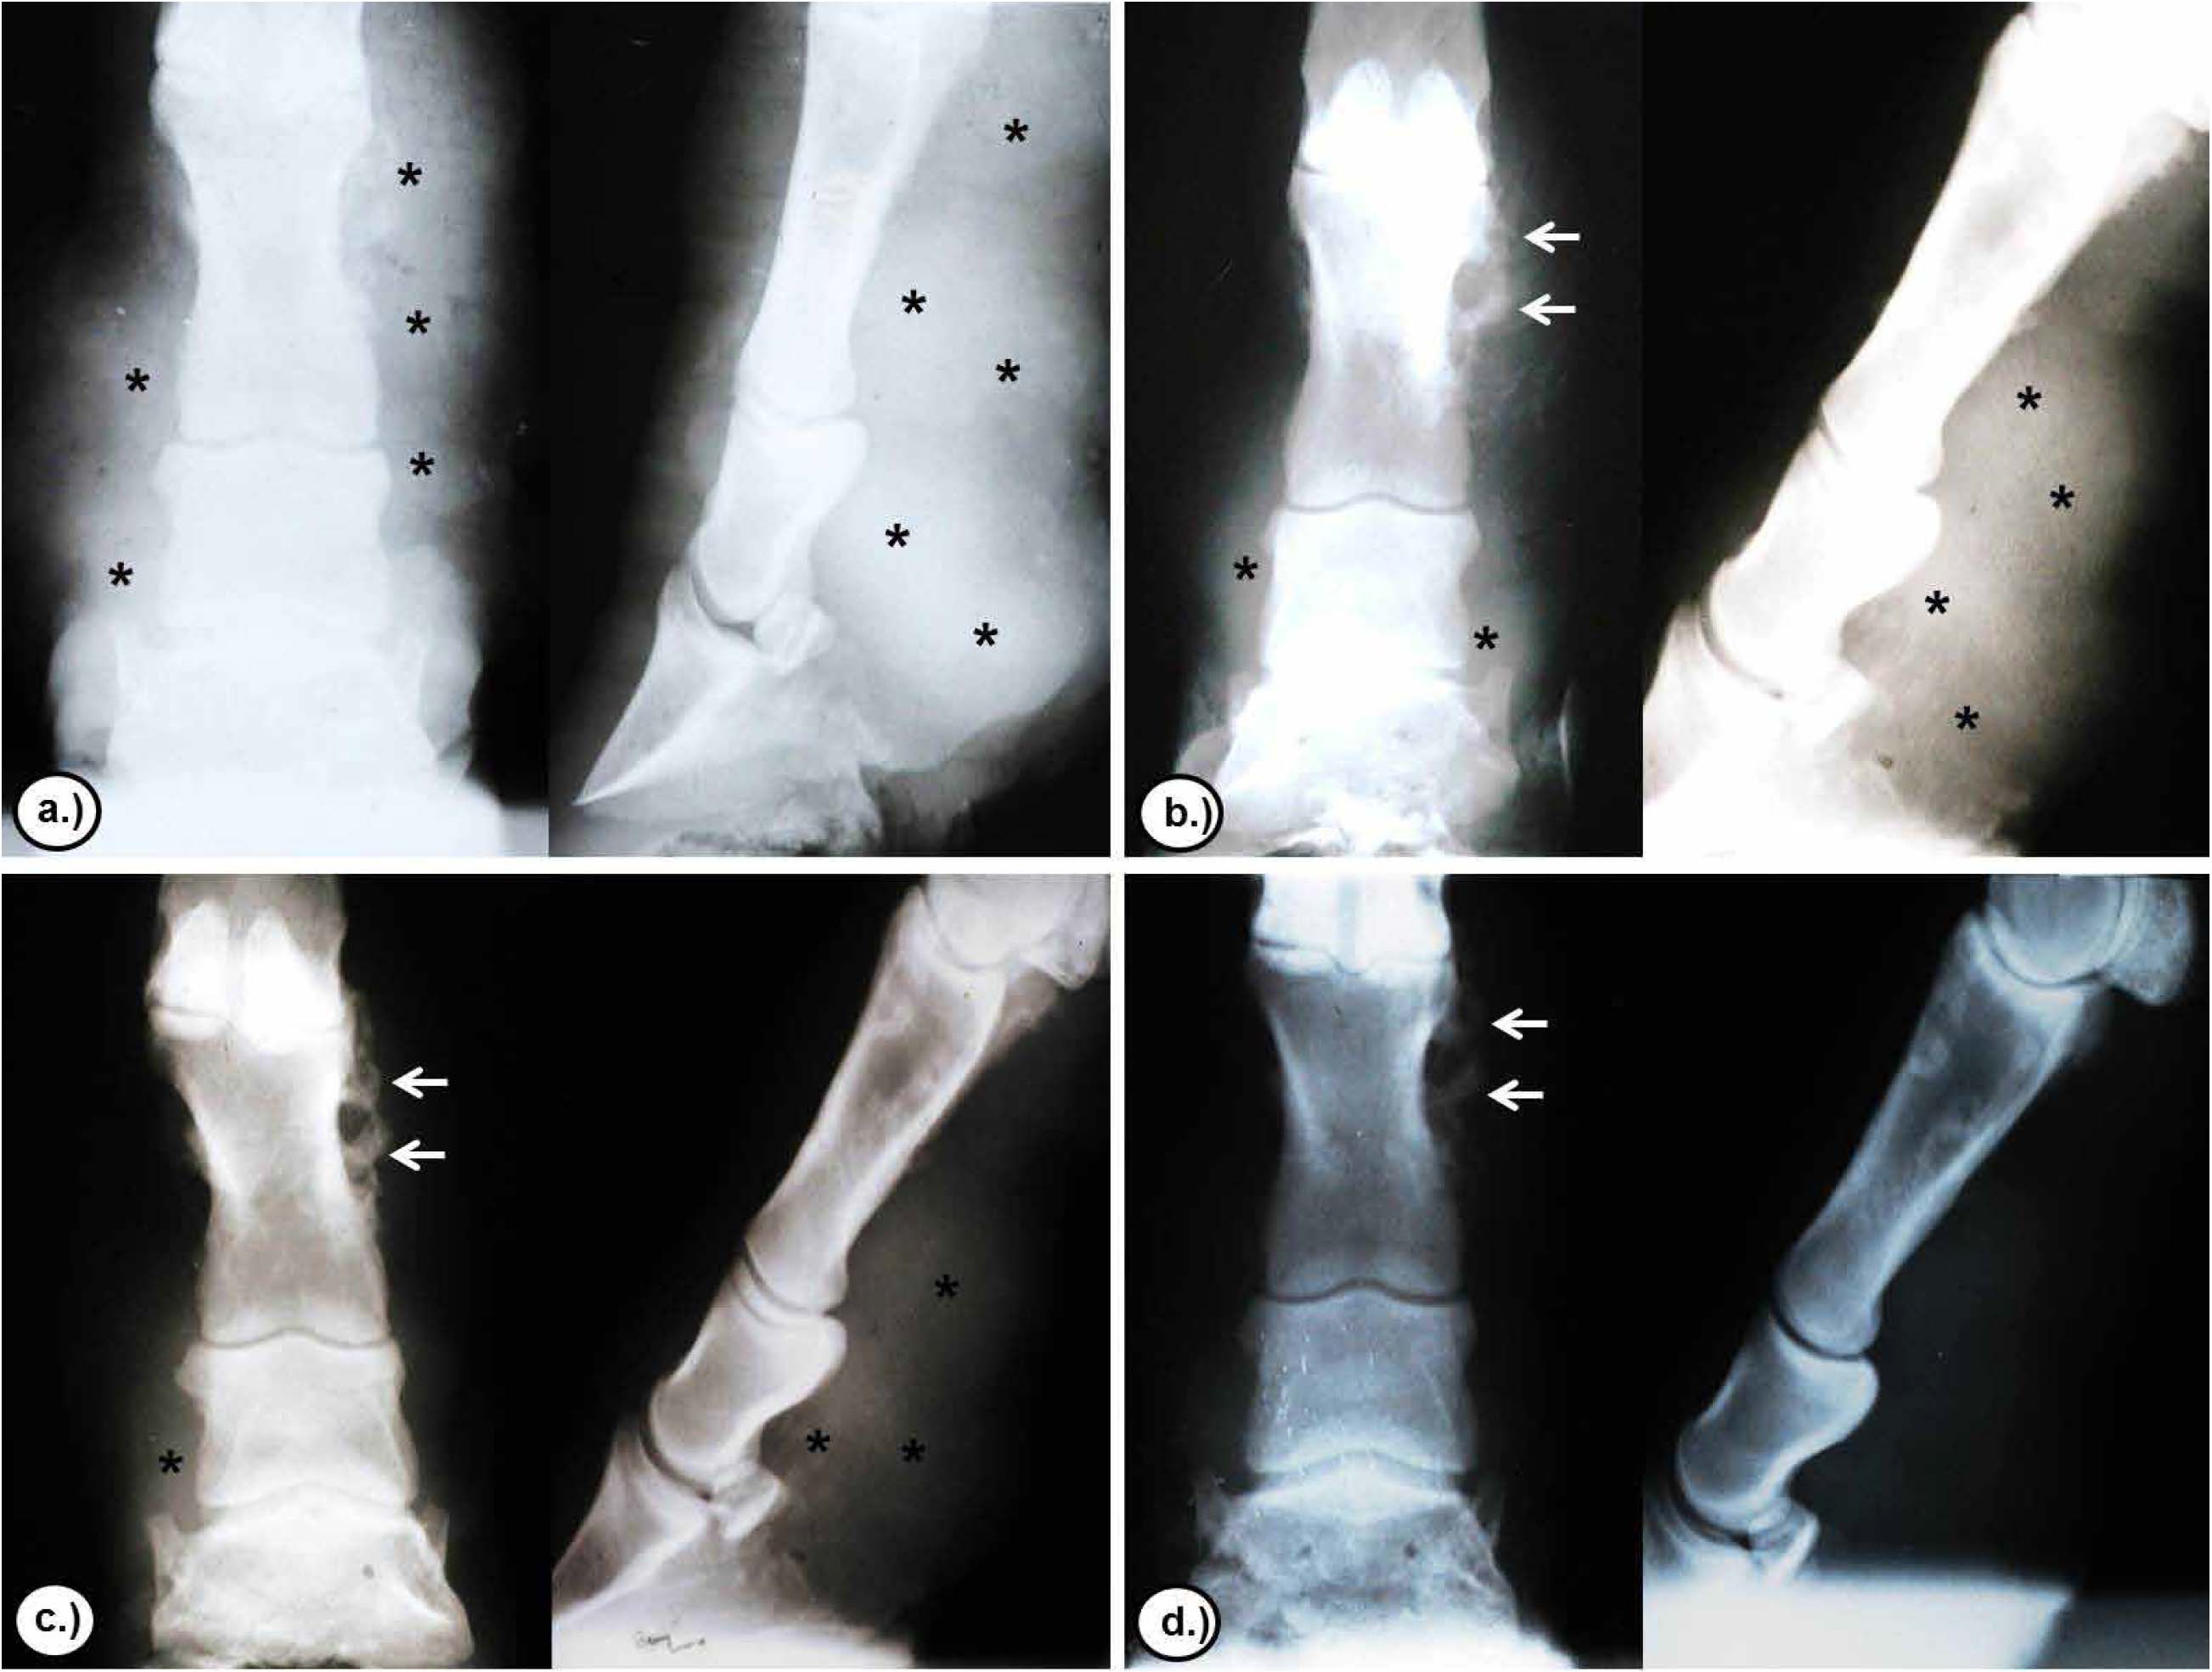

Regarding the radiological follow-up of chronic cutaneous lesions located in the distal parts of 3 animals in the study, the dorsum-palm and lateral-medial projections showed the development or invasion of the underlying tissues compromising bone structures, which were characterized by tissue fibrosis, moderate exostosis, as well as by osteolysis and osteomyelitis in some areas, in agreement with Zaro (20), who reported irregularities in the bone surface with severe erosions and periosteal reactions in chronic pythiosis cases in horses.

After treatment with triamcinolone acetonide, moderate radioactivity and presence of enthesophytes was observed at day 16 in the cortex of the bone. At day 32 the decrease in radio-opacity areas was more marked, and at day 64 radio-opacity was absent in the tissue, although small focal areas of radio-opacity were evident in the cortex of the bone, indicating a decrease in tissue fibrosis and the presence of exostoses as sequelae of the chronicity (Figure 7).